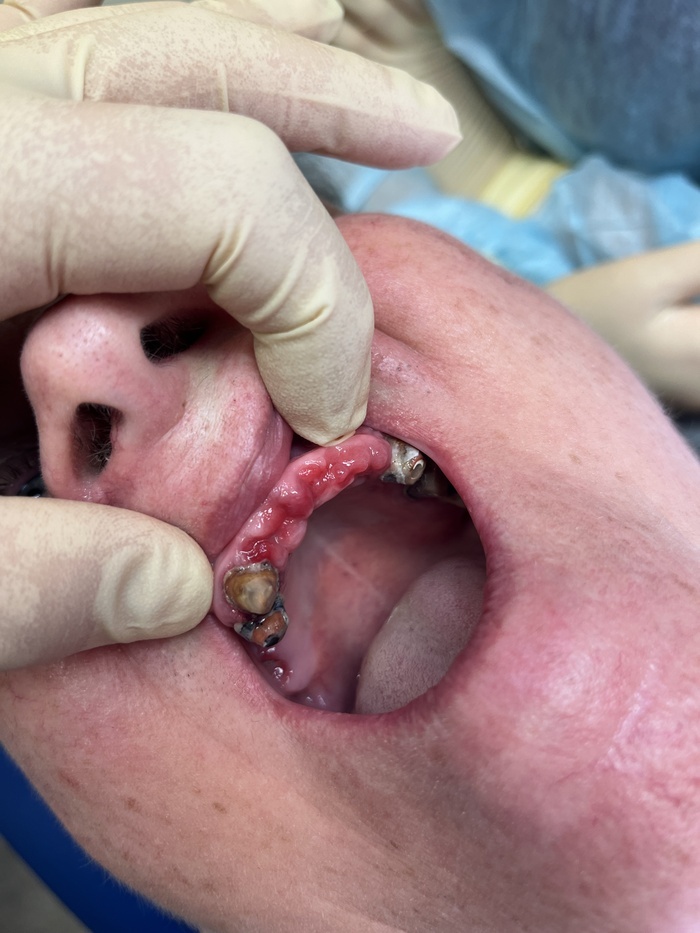

Сняли мы с пациенткой верхний протез с подобным «седлом». Вот, что уже 15 лет живет под ним. Вычистить все это нереально при всем желании даже у врача в кресле.

А вот так выглядит десна под ним.